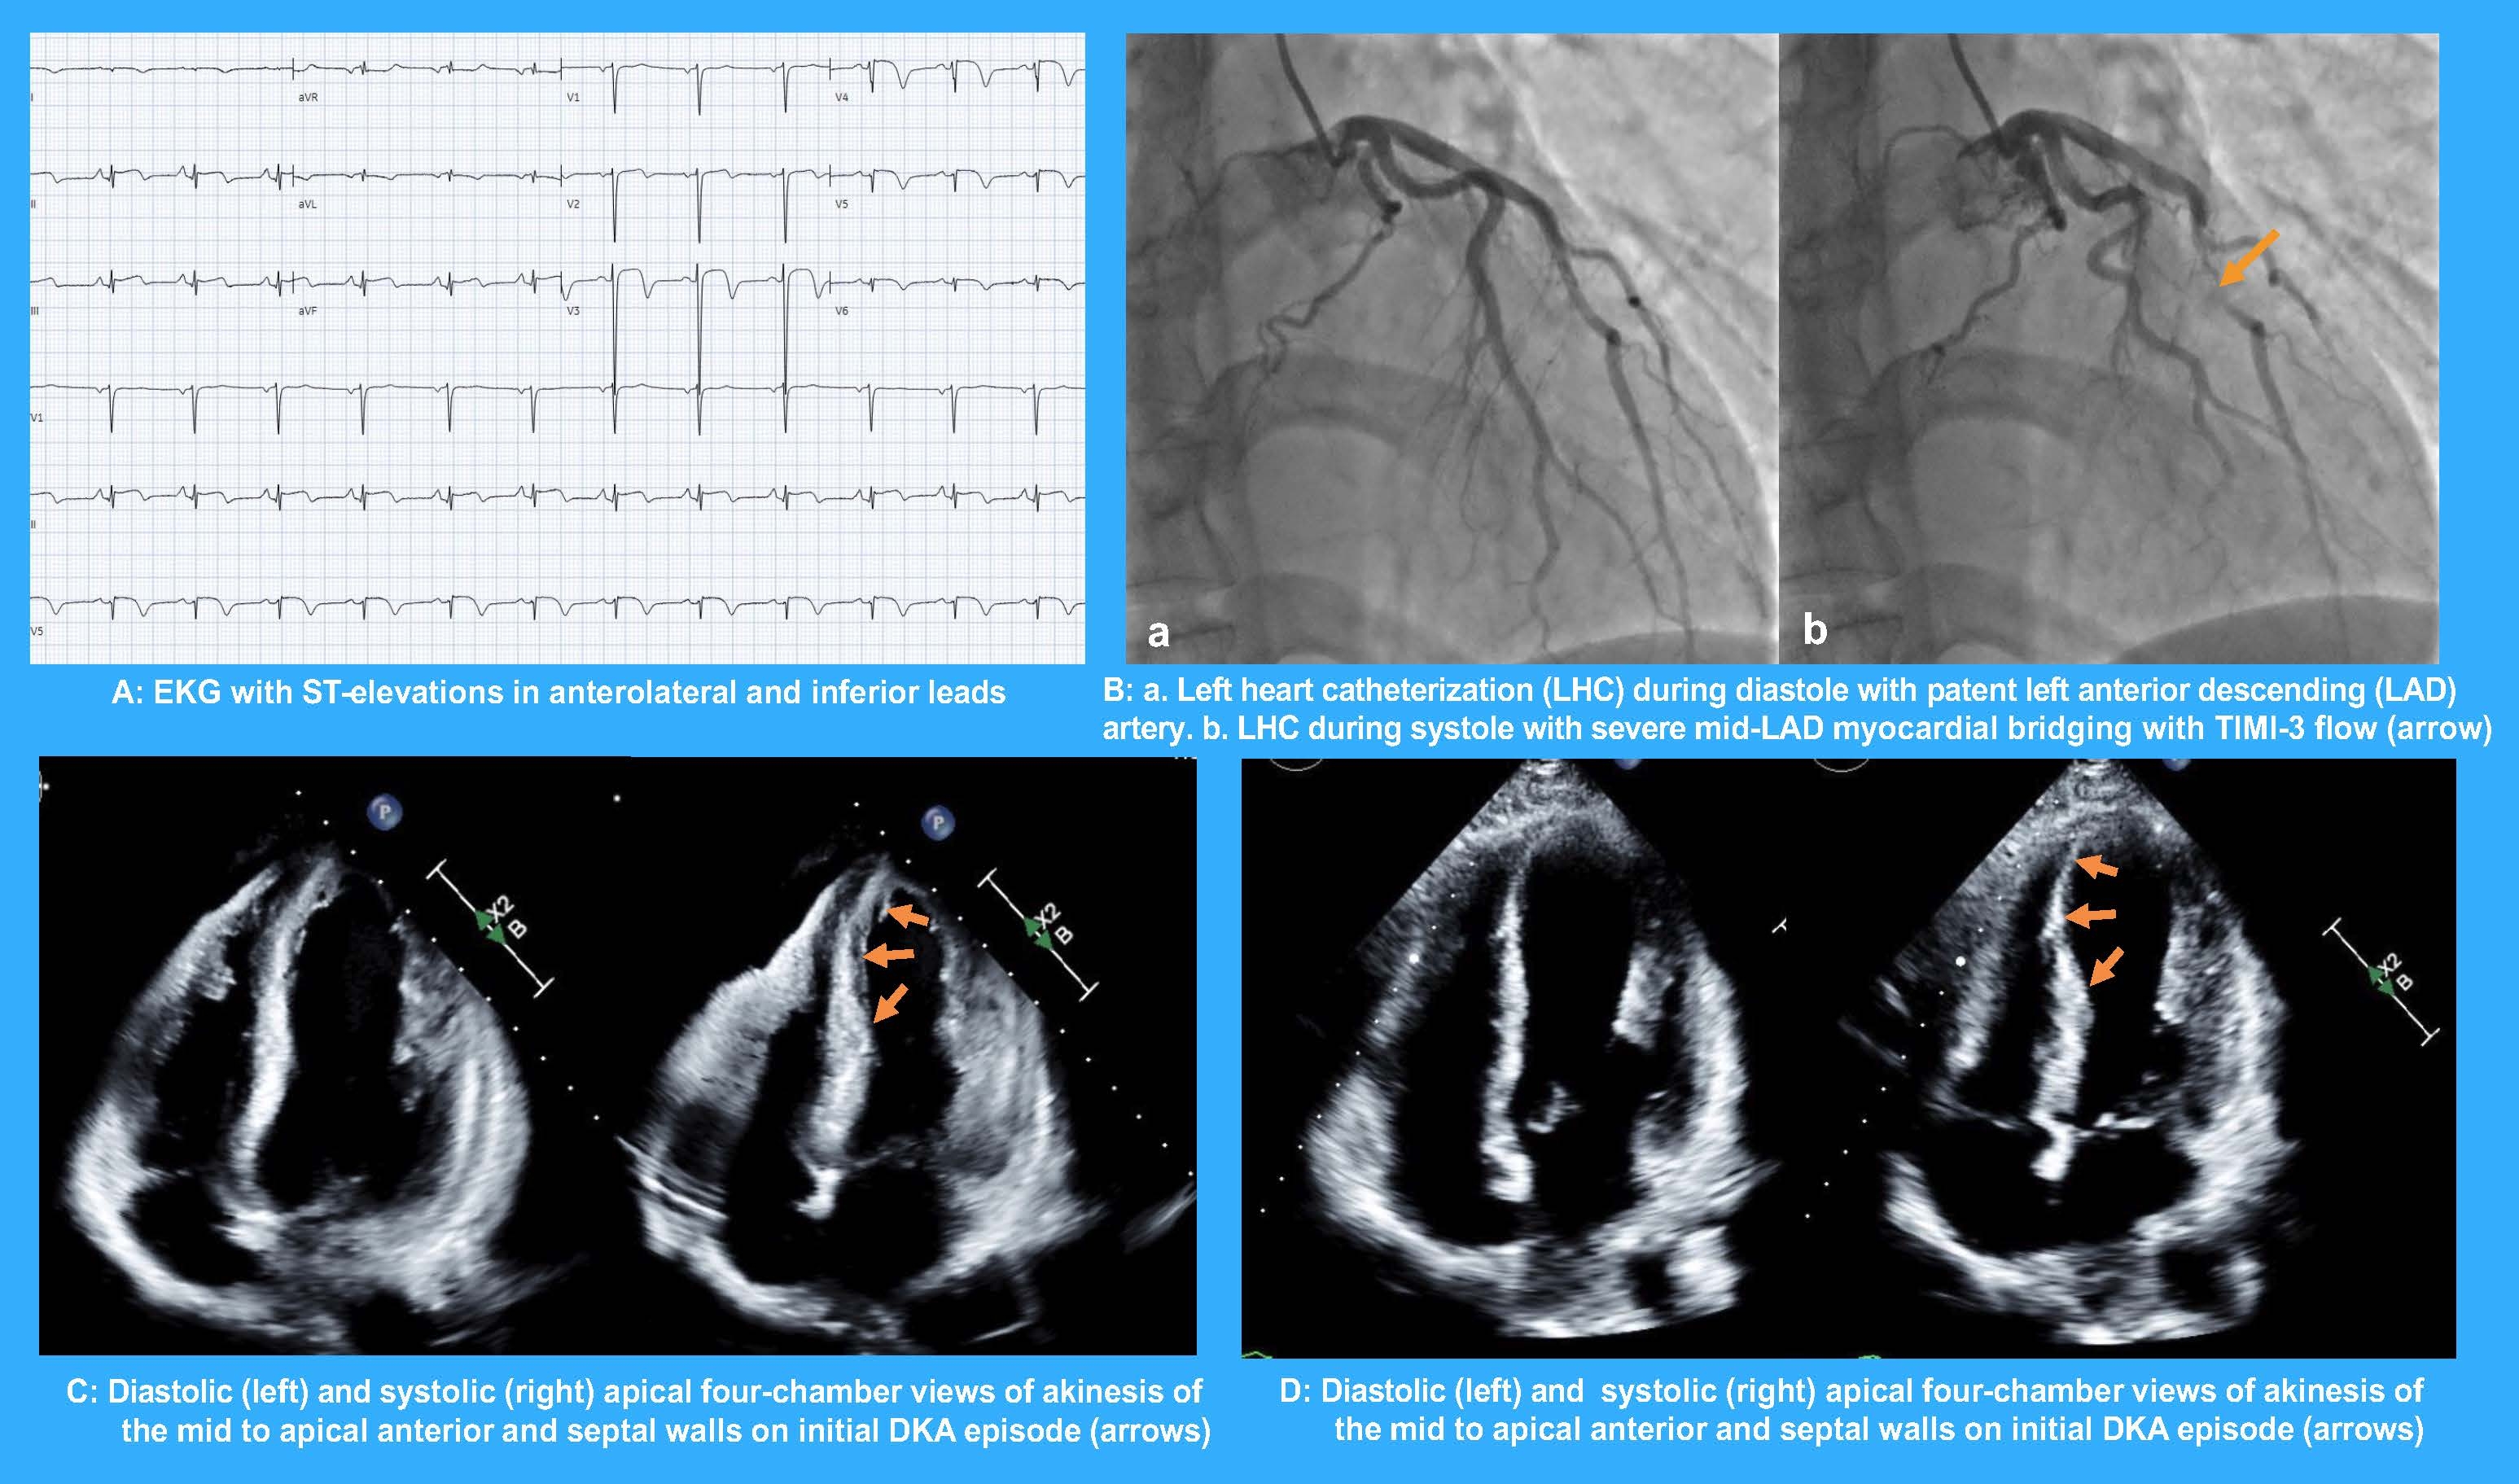

Case presentation: A 47-year-old male with a history of type 1 diabetes mellitus was admitted to the Intensive Care Unit for diabetic ketoacidosis (DKA). He complained of epigastric pain with an electrocardiogram showing transient ST-elevation in the anterior and inferior leads. Cardiac troponin showed an upward trend with a peak of 0.202 ug/L and an elevated NT-proBNP of 5,014 pg/mL. A transthoracic echocardiogram (TTE) revealed left ventricular systolic dysfunction (LVEF 40%) with akinesis of the mid to apical anterior and septal walls, consistent with the left anterior descending (LAD) artery territory. Emergent left heart catheterization (LHC) revealed patent coronary arteries with severe mid-LAD MB with TIMI 3 flow. He was managed conservatively with guideline-directed medical therapy for heart failure, and subsequent TTE nine months later showed normalization of LV wall motion (LVEF 65%). Five months later, the patient was readmitted for DKA with elevated troponin. A repeat TTE demonstrated LV systolic dysfunction (LVEF 35%) with wall motion abnormalities (WMA) mirroring the initial presentation.

Discussion: Our patient presented with recurrent episodes of ACS/MS complicated by LV systolic dysfunction along the LAD territory during periods of DKA, a known stressor for myocardial ischemia. The absence of obstructive coronary atherosclerosis on LHC, coupled with severe mid-LAD MB, suggests that the MB was the likely culprit for recurrent ACS/MS. Although stress cardiomyopathy was considered a differential diagnosis, this was less likely given the uncharacteristic pattern of WMA sparing the apical lateral and inferior walls as opposed to apical ballooning and the presence of an alternative diagnosis.